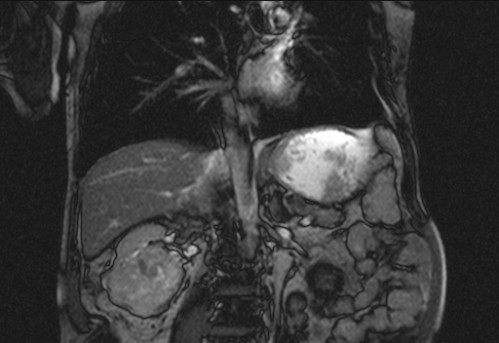

Auffälliges Abdomen bei der Vorsorgeuntersuchung einer älteren Dame

ICD: C64

68 Jahre alte Frau. Sie geht zur Darmspiegelung im Rahmen ihrer Krebsvorsorgeuntersuchung. Der Internist bemerkt bei der ergänzenden sonografischen Untersuchung des Abdomens einen auffälligen Befund.